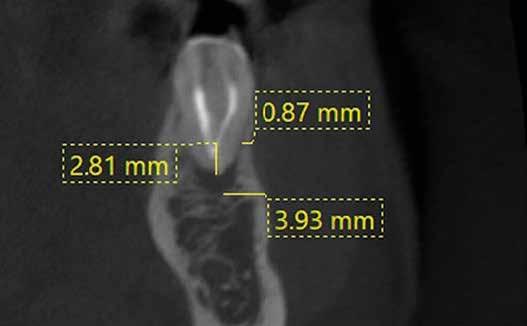

A fogszabályzó kezelések egyik legfontosabb célja, hogy elérjük a lehető legharmonikusabb interokkluzális fogérintkezéseket, továbbá az állcsont relációs helyzetének frontális és szaggitális síkban is megfelelőnek kell lennie. A fogszabályzás befejezésekor a fogpozícióknak nem orthodonciai, hanem protetikai szempontok szerint kell ideálisnak lenniük. Az Invisalign ClinCheck szoftver (Align Technology) segítségével a protetikus az orthodontussal együtt meg tudja határozni azokat a végső fogpozíciókat, amelyek a lehető legjobb végeredmény biztosításához elengedhetetlenek. Bizonyos klinikai paramétereket, mint a fogak klinikai koronájának nagyságát, az egyes fogak fogíven belüli optimális pozícióját, a fogívek egymáshoz viszonyított helyzetét, a fogak között látható rések nagyságát, a frontfogak tengelyének dőlését, az overjet és overbite mértékét már a kezelések megkezdése előtt pontosan definiálni kell. Ezeket az adatokat viszont csak a tervezett végleges fogpótlás ismeretében lehet meghatározni, ezért van szükség az orthodontus és a protetikus szoros együttműködésére.